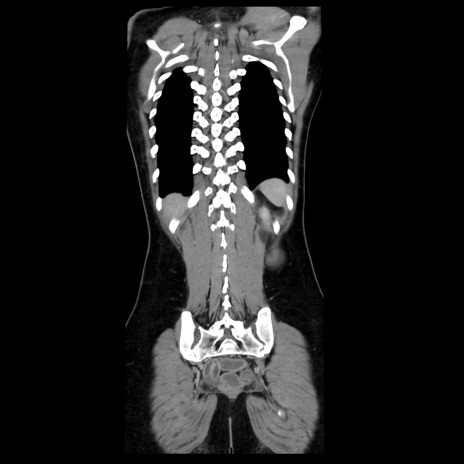

症例39(冠状断像)

【症例】40歳代女性

【主訴】上下腹部痛

【現病歴】2日目から下腹部痛あり。夜間は痛みで眠れなかった。昨日より上腹部痛と下痢が出現。臥位で痛みは軽快したため、休んでいた。本日になって臥位でも立位でも痛みが強くなってきたため救急要請。

【既往歴】子宮内膜症

【身体所見】部:平坦・軟、左上下腹部に圧痛あり、反跳痛あり。

【データ】WBC 21800、CRP 26.78

CT